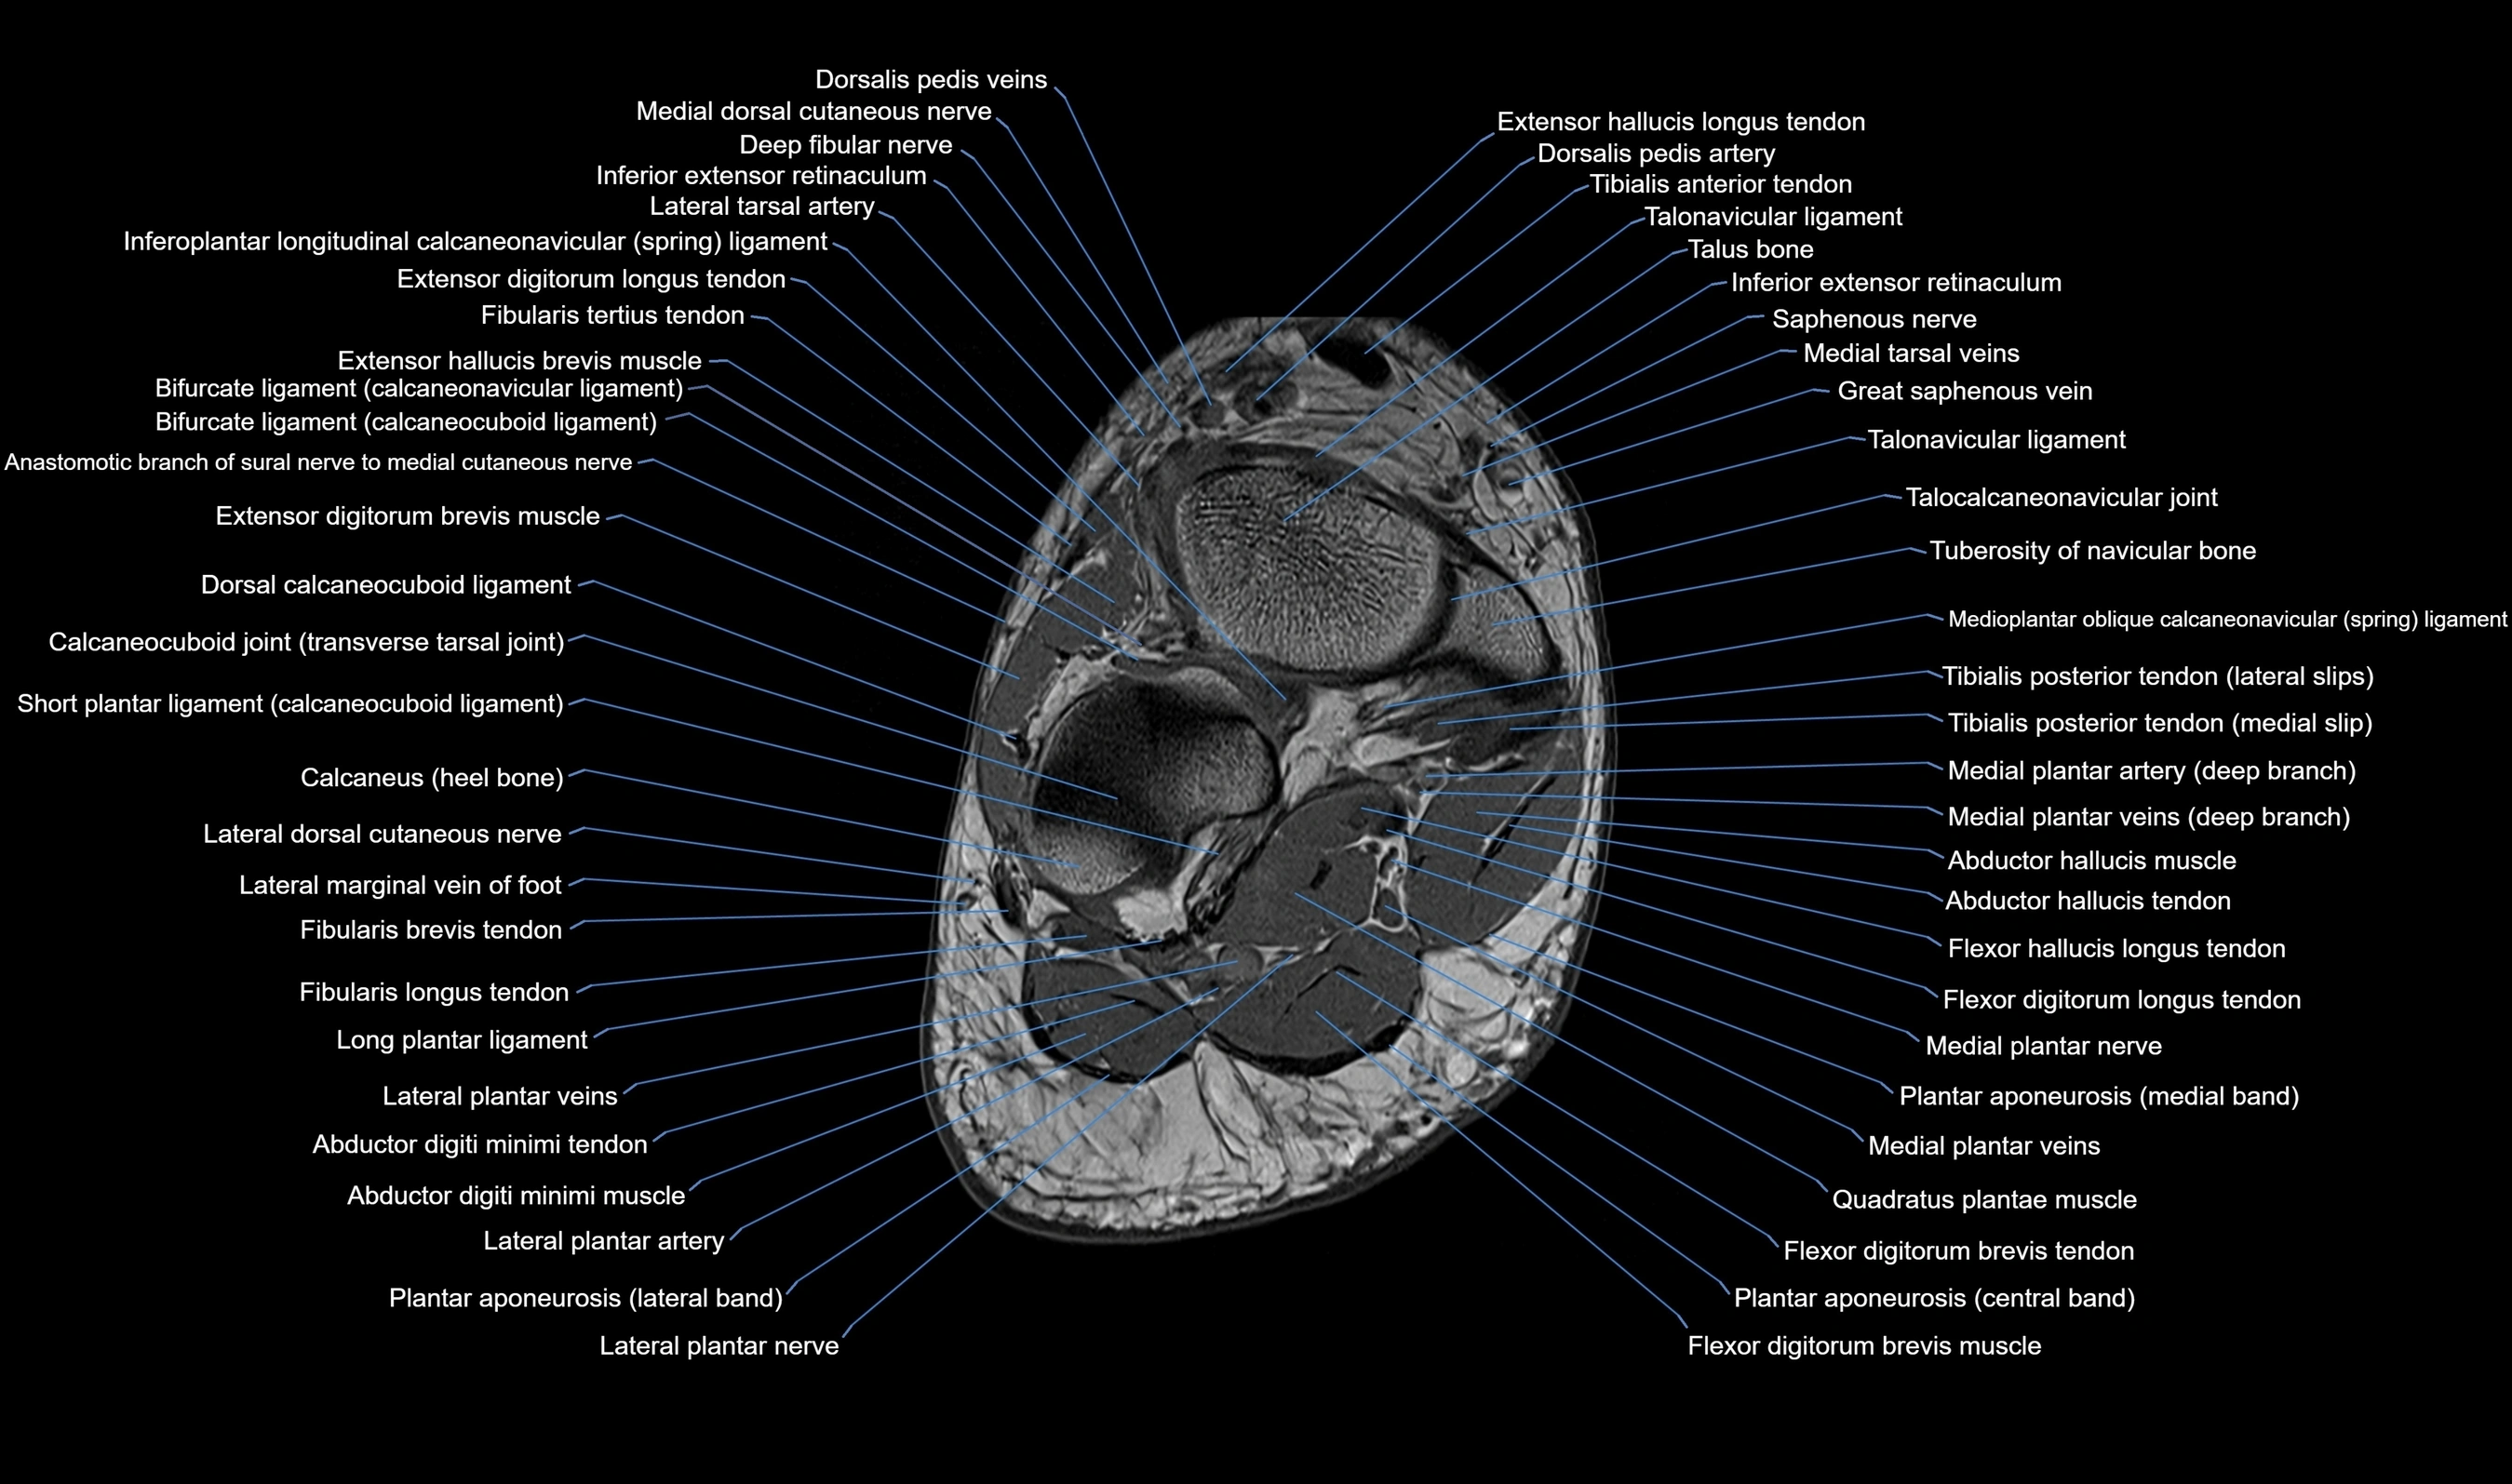

MRI image